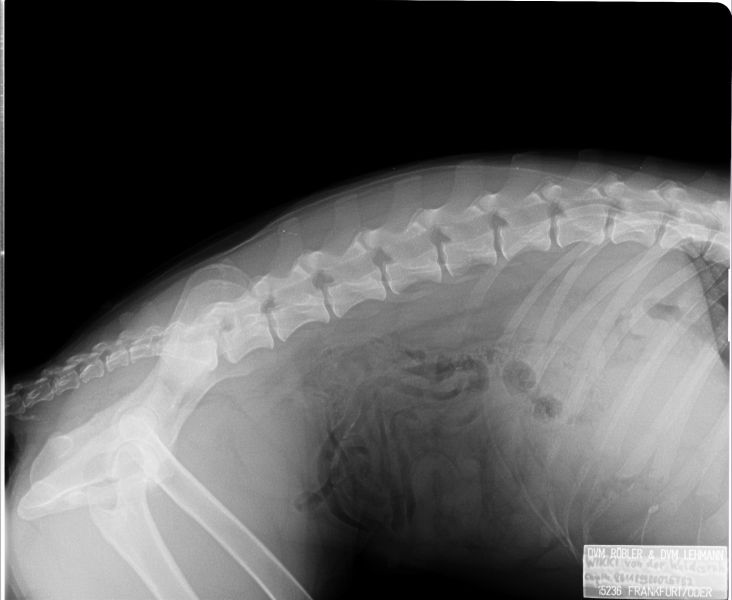

Auswertung der Röntgenbilder von Wikki  aus Augsburg:

HD- fast normal; ED-normal